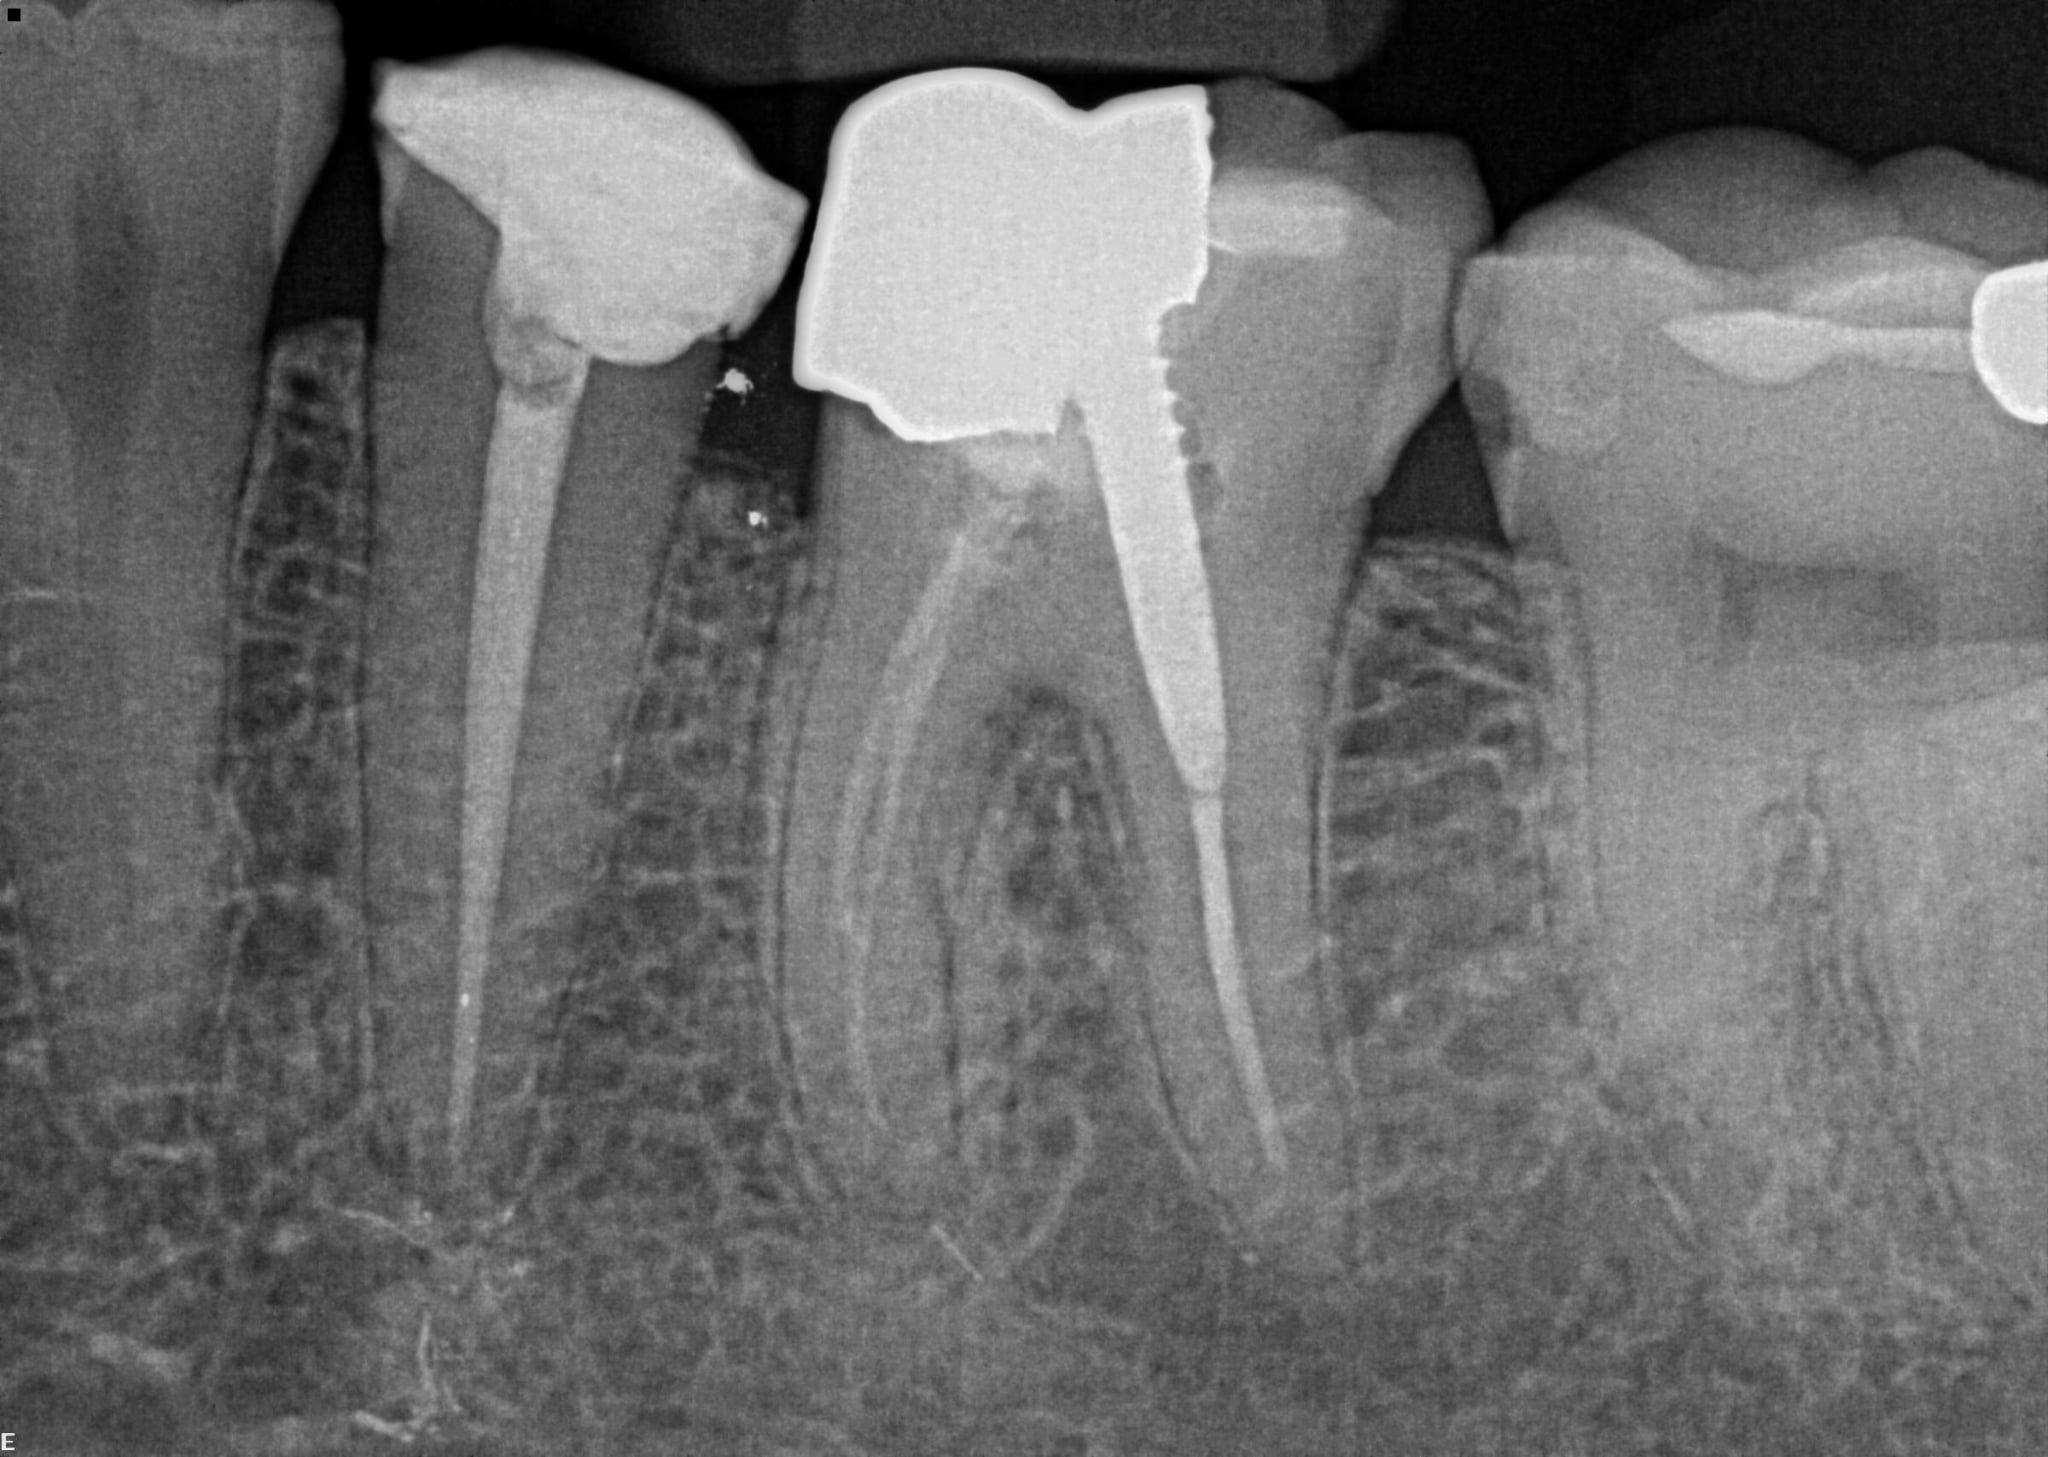

3 / 50

3. (Select ONE OR MORE correct answers)

The radiograph shows evidence of calculus on

4 / 50

4. (Select ONE OR MORE correct answers)